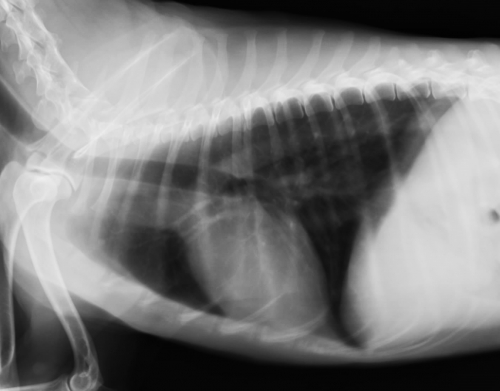

下の写真は悪性皮膚メラノーマの肺転移のレントゲン写真です。(今回のトピックとは違うワンちゃんのものです。)上が肺転移以前の正常なレントゲン画像、下がメラノーマによる転移性肺がんの写真です。本来黒く抜けて見える肺に砲弾状に白く見える転移病巣が多数みられています。

悪性メラノーマの肺転移による主な症状は呼吸不全です。進行は早く、呼吸器症状の発生から数週間以内に転移病巣による肺への直接の障害やそれに伴う肺炎、胸膜炎、胸水などにより重篤な状態に至ってしまいます。